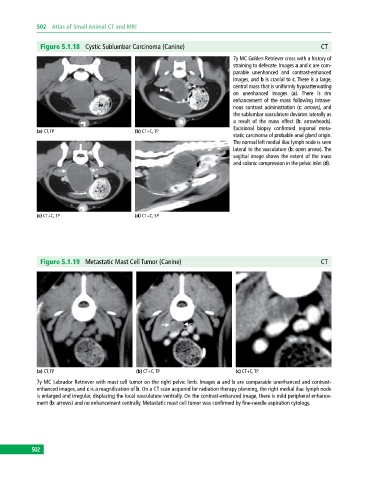

Figure 5.1.18 Cystic Sublumbar Carcinoma (Canine) CT

7y MC Golden Retriever cross with a history of

straining to defecate. Images a and c are com

parable unenhanced and contrastenhanced

images, and b is cranial to c. There is a large,

central mass that is uniformly hypoattenuating

on unenhanced images (a). There is rim

enhancement of the mass following intrave

nous contrast administration (c: arrows), and

the sublumbar vasculature deviates laterally as

a result of the mass effect (b: arrowheads).

Excisional biopsy confirmed regional meta

(a) CT, TP (b) CT+C, TP

static carcinoma of probable anal gland origin.

The normal left medial iliac lymph node is seen

lateral to the vasculature (b: open arrow). The

sagittal image shows the extent of the mass

and colonic compression in the pelvic inlet (d).

(c) CT+C, TP (d) CT+C, SP

Figure 5.1.19 Metastatic Mast Cell Tumor (Canine) CT

(a) CT, TP (b) CT+C, TP (c) CT+C, TP

7y MC Labrador Retriever with mast cell tumor on the right pelvic limb. Images a and b are comparable unenhanced and contrast

enhanced images, and c is a magnification of b. On a CT scan acquired for radiation therapy planning, the right medial iliac lymph node

is enlarged and irregular, displacing the local vasculature ventrally. On the contrast‐enhanced image, there is mild peripheral enhance

ment (b: arrows) and no enhancement centrally. Metastatic mast cell tumor was confirmed by fine‐needle aspiration cytology.